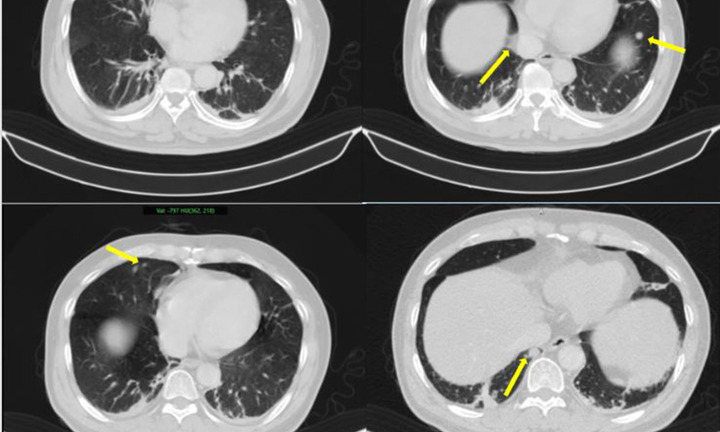

Trường hợp của một phụ nữ ở Hồ Nam (Trung Quốc) cho thấy ứng dụng trí tuệ nhân tạo (AI) có thể giúp phát hiện sớm ung thư phổi, tạo cơ hội điều trị hiệu quả.

Ung thư phổi nếu được phát hiện từ giai đoạn sớm chỉ cần phẫu thuật, không cần xạ hay hóa trị, người bệnh có thể sống thêm nhiều năm.